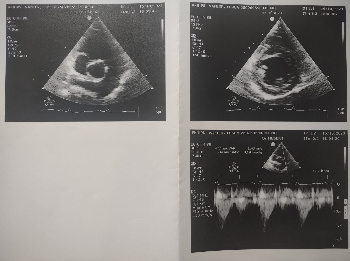

STÉNOSE PULMONAIRE TOSCA